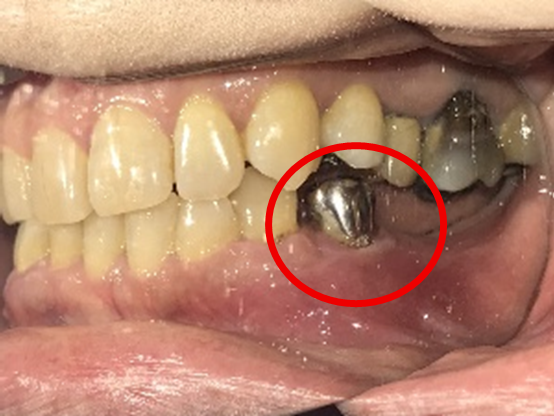

Before

※赤丸を抜歯しました。

After